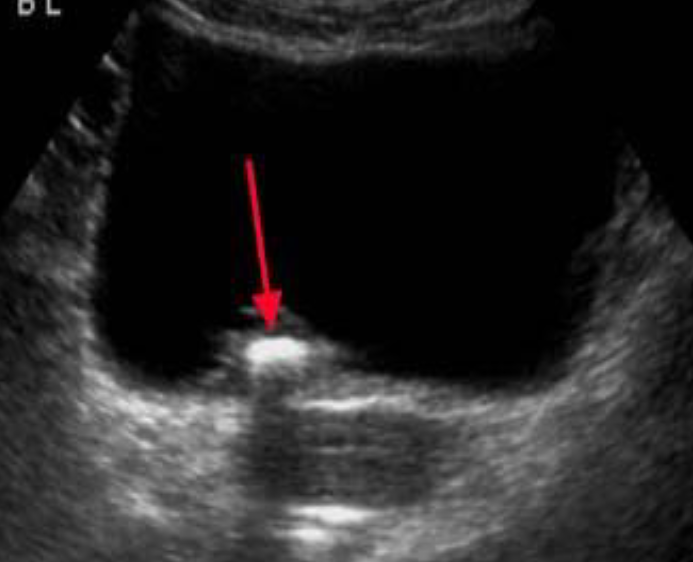

Ultrasound - Bladder calculus